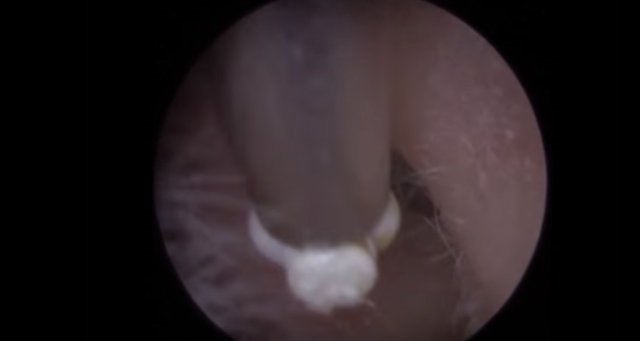

30 yıl boyunca geçmeyen bir baş ağrısı ile yaşayan bir kişi gittiği doktoru şoke etti. Yıllarca baş ağrısı çeken 59 yaşındaki adamın yaşadıkları kan dondurdu. Adamın kafasından öyle bir şey çıktı ki, doktorlar bile şaştı kaldı. İşte şoke eden olayın detayları...